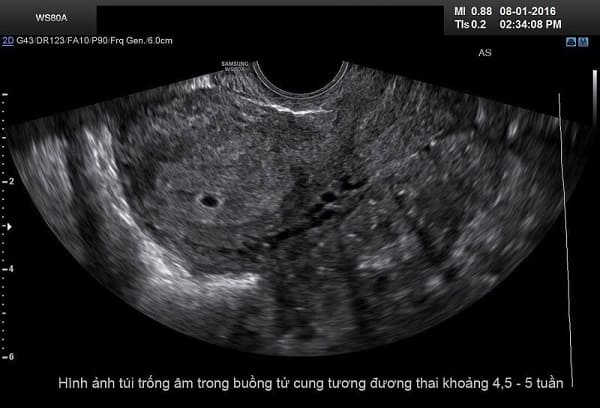

Bác sĩ phòng khám 152 Xã Đàn cho biết: Mang thai 5 tuần tuổi có thể phá được khi thai đã vào tử cung. Phương pháp phá thai an toàn đối với trường hợp thai 5 tuần tuổi đó là phá thai nội khoa.

Thông qua việc thăm khám sẽ giúp bác sĩ xác định được độ tuổi của thai nhi; nắm bắt được tình trạng sức khỏe của thai phụ.